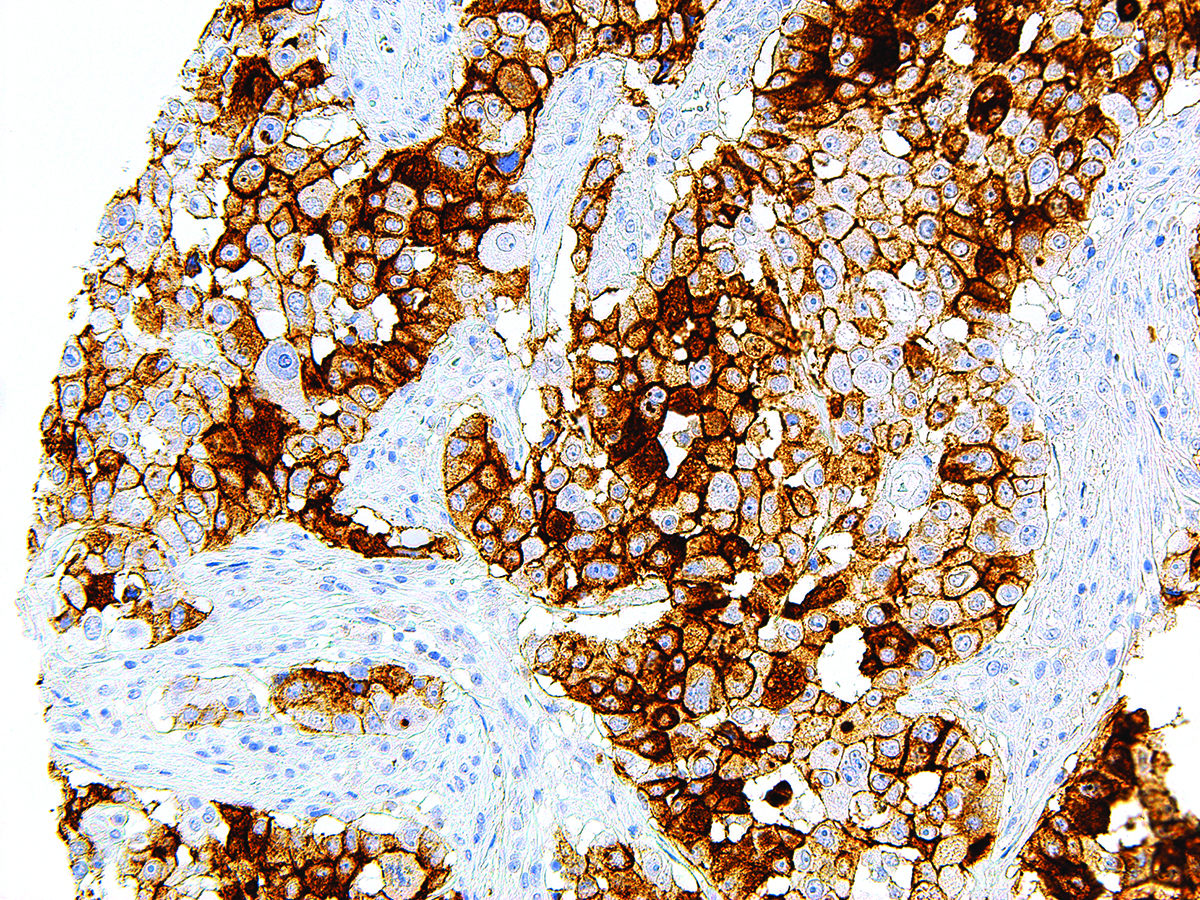

| Positive Control | Ovarian Serous Carcinoma |

CA-125 is normally found in epithelial cells of Fallopian tube, endometrium and endocervix, pancreas, colon, gall bladder, stomach, kidney, apocrine sweat gland, mammary gland, and mesothelial cell lining of pleura, pericardium and the peritoneum. Staining with CA-125 reacts positively with ovarian malignancies, cervical carcinoma, endometrial and bladder adenocarcinoma, seminal vesicle carcinoma, and anaplastic lymphoma.